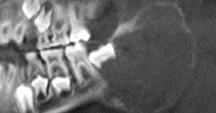

Fig.16 Radiotransparenta Fig.17 Radiotransparenta corespunzatoare

corespunzatoare unui chist folicular unui chist folicular al molarului 1.8

(dentiger) al caninului superior.

Varianta cu extensie laterala este prezenta in cazul unui molar de minte inferior semiinclus, in care radiotransparenta intereseaza doar portiunea distala a dintelui, spre ramul mandibular.